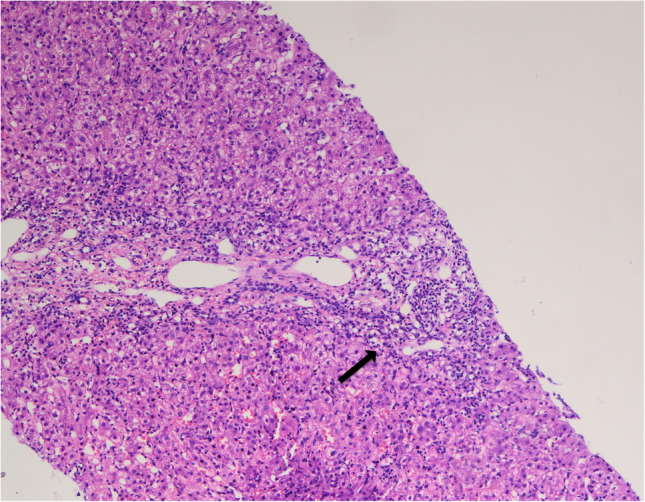

The three major autoimmune liver diseases are autoimmune hepatitis (AIH), primary biliary cholangitis (PBC), and primary sclerosing cholangitis (PSC).These conditions are assumed to result from a breakdown in immunological tolerance, which leads to an inflammatory process that causes liver damage.The self-attack is started by T-helper cell-mediated identification of liver autoantigens and B-cell production of autoantibodies,and it is maintained by a reduction in the number and activity of regulatory T-cells.Infections and environmental factors have been explored as triggering factors for these conditions, in addition to a genetic predisposition.Allelic mutations in the HLA locus have been linked to vulnerability, as have relationships with single nucleotide polymorphisms in non-HLA genes.Despite the advances in the management of these diseases, there is no curative treatment for these disorders, and a significant number of patients eventually progress to an end-stage liver disease requiring liver transplantation.In this line, tailored immune-therapeutics have emerged as possible treatments to control the disease.In addition, early diagnosis and treatment are pivotal for reducing the long-lasting effects of these conditions and their burden on quality of life.Herein we present a review of the etiology, clinical presentation, diagnosis, and challenges on ALDs and the feasible solutions for these complex diseases.